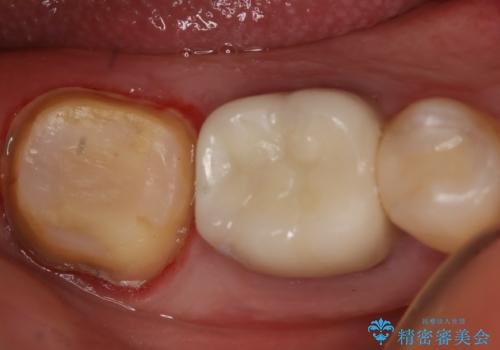

- 咬んだ時に右下奥歯に痛みがあるとの事で来院された患者様です。

歯の神経は壊死していたため、精密根管治療と補綴治療を計画しました。

セラミックでの治療を希望されたので補綴はオールセラミッククラウンでの治療を選択しました。